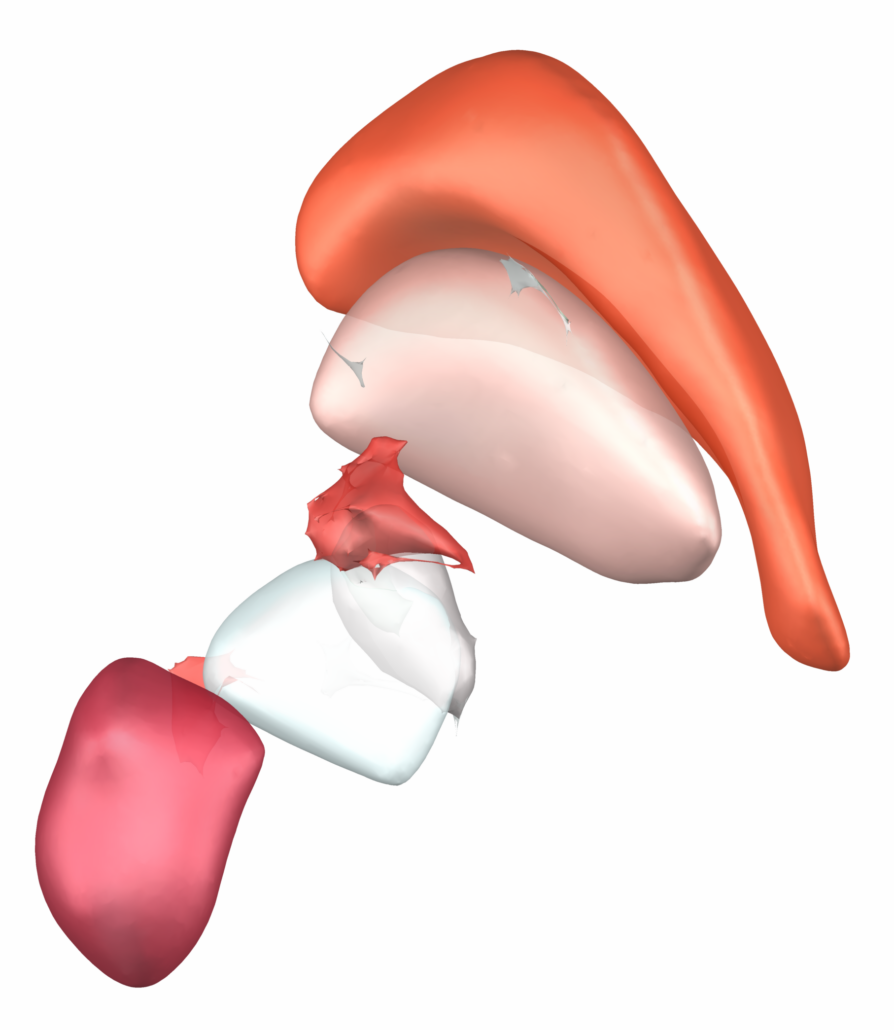

Subsection of the DISTAL atlas visualized with three typical DBS electrodes